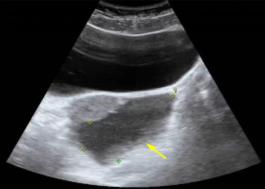

患者43岁,一周来无明显诱因出现左下腹痛,无阴道流血流液,无畏寒发热,无恶心呕吐,发病以来食纳规整,排气排便畅。患者既往体健,否认慢性疾病史,否认腹盆腔手术史,生育史:2-0-1-2,阴道分娩。否认相关家族遗传疾病史。初诊查B超提示:盆腔偏左侧见80mm×65mm×62mm无回声区,内见多个线样分隔带,曾于我院抗炎治疗,但病情未完全缓解,复查B超盆腔肿物未见缩小(图1),遂门诊收住入院进一步诊治。

妇科蛋白膜怎么用这种妇科肿瘤无特异性,复发率高,有这些症状的姐妹小心_https://www.jmylbn.com_新闻资讯_第1张图1 B超见子宫左后方囊性灶,

内可见分隔带(箭头所示)